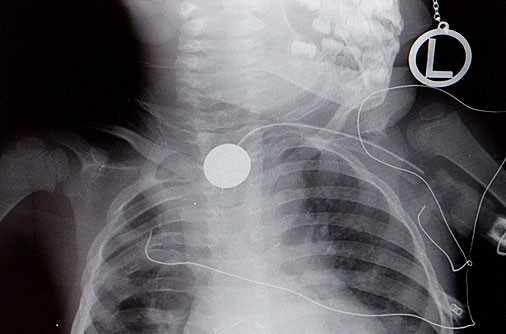

(Poza 8) Un rus s-a trezit ca, dupa ce a crezut mereu ca are cancer, doctorii i-au scos din plaman... un copacel de cinci centimetri! Radiografiile aratau ca avea ceva, ca o tumora, pe plaman si toti credeau ca e canceroasa. Au vrut sa il opereze si, dupa ce au taiat o portiune din organ, ca sa ii faca biopsia, au descoperit minunea.